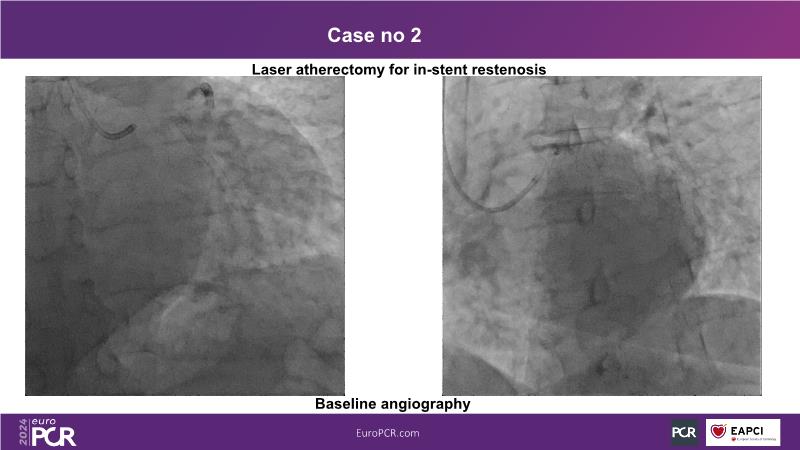

In this session, discover the effectiveness and safety of robotic PCI for both simple and complex lesions requiring additional devices like IVL, IVUS, laser, and FFR. Learn about the numerous benefits of robotics for patients and cathlab teams, including enhanced precision in wire navigation and stent positioning, full radioprotection, and reduced orthopedic injuries. Explore the growing interest in robotics within the interventional cardiology community, anticipate future technical advancements, and understand how AI will accelerate the integration of robotics and vice versa.